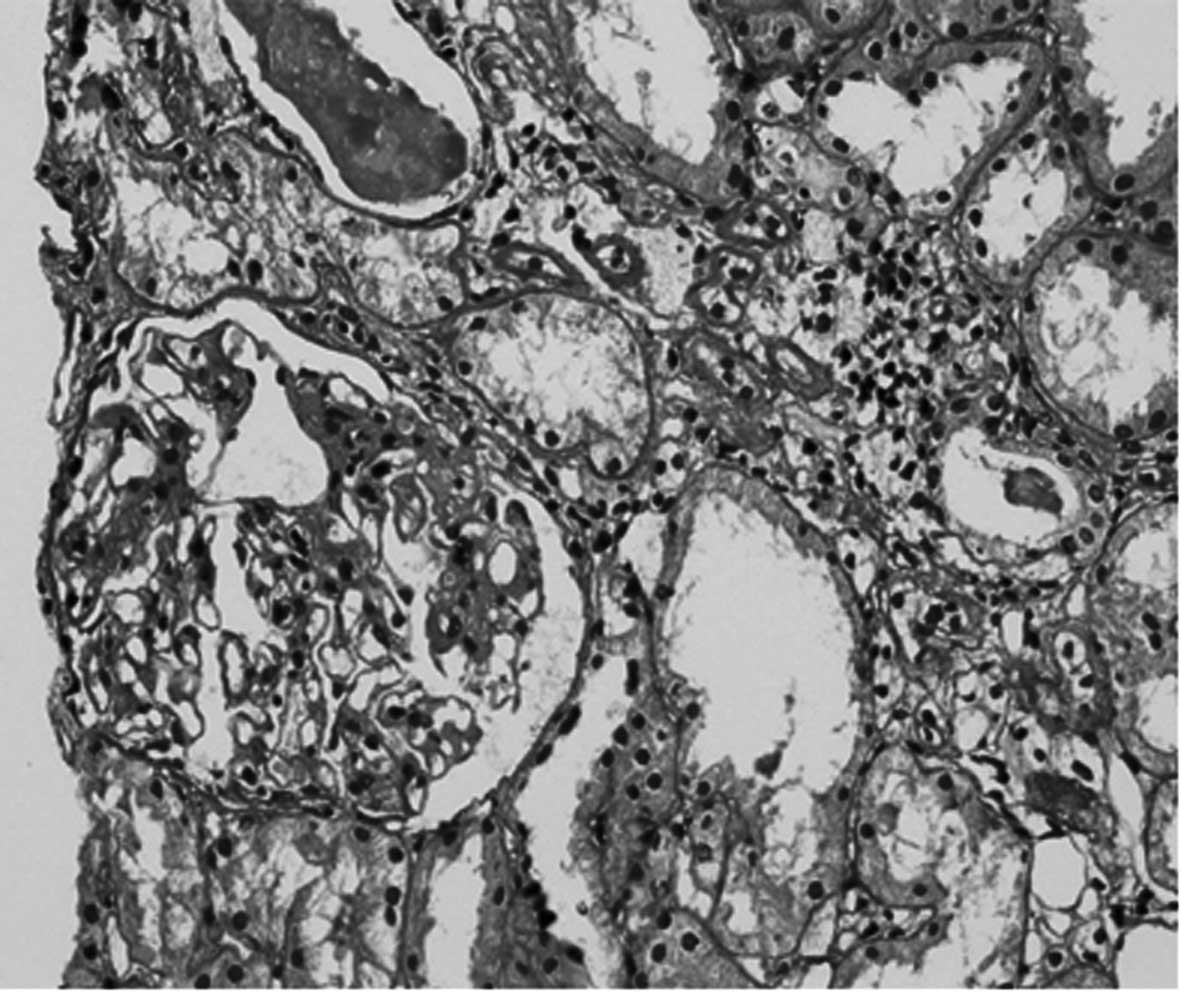

viral infection. The diagnosis of MsPGN was based on light

microscopy findings of increased mesangial cells and matrix levels

[using hematoxylin and eosin (HE), Periodic acid-Schiff (PAS) and

The clinical diagnosis of MsPGN was made by the

histological examination of each renal biopsy. Fig. 1 shows a patient renal biopsy slide

with glomerular mesangial proliferation stained with PAS. The